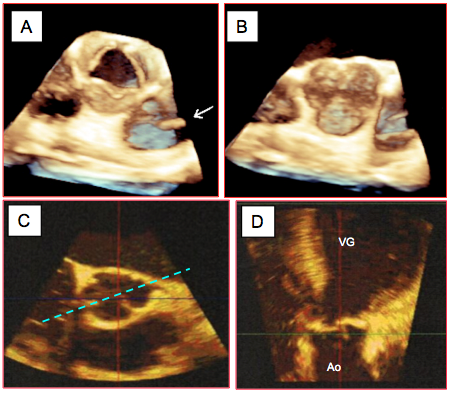

Figure 26.75 : Vues ETO 3D de la valve aortique. A: vue "en-face" depuis la racine de l'aorte en systole; cette vue correspond au court-axe 40°. B : même vue en diastole. La flèche indique la présence d'un cathéter pulmonaire dans l'AP. C : court-axe de l’anneau aortique (plan transverse); le traitillé indique le plan de coupe coronal. D : long-axe de l’anneau (plan coronal) ; ce plan n’est pas réalisable en ETO 2D.